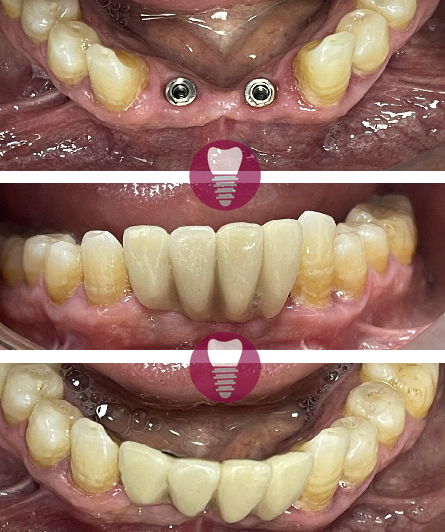

4.1 – Implante dental de incisivo superior

Los implantes dentales son una solución avanzada para la pérdida de piezas dentales. Este procedimiento consiste en la colocación de una raíz artificial de titanio en el hueso maxilar, sobre la cual se instala una corona dental personalizada que imita a la perfección la forma y color del diente original. Este tratamiento es ideal para restaurar incisivos superiores, devolviendo la funcionalidad y estética de la sonrisa de manera natural y duradera.